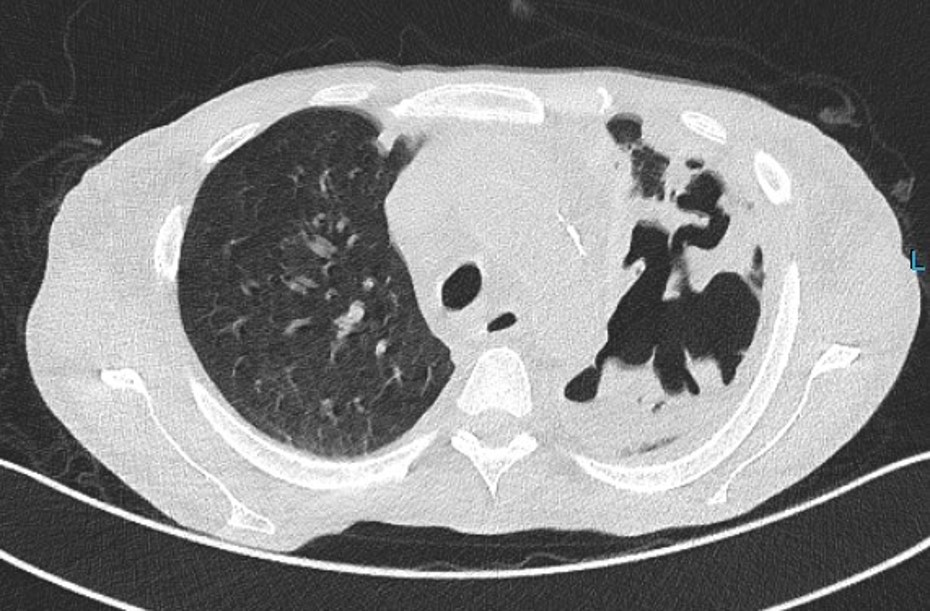

Results: Methylprednisolone was initiated then anti-thymocyte globulin and adalimumab were added. Bacterial, viral and fungal prophylaxis were given. The patient recovered and discharged in good conditions. Five months later the patient developed acute severe pneumonia with extensive lung necrosis that required mechanical ventilation but progressed to refractory respiratory distress and the patient died after 6 months following liver transplantation.